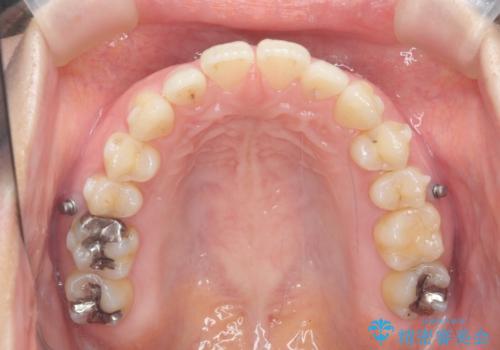

- 出っ歯に見える前歯を治したい、と矯正治療を希望され来院されました。

奥歯の噛み合わせに大きな問題はないので、目立つ前歯の角度・隙間を重点的に整え、審美的な歯並びを獲得できるよう計画します。

治療によりしっかりと前歯の角度が改善され、審美的な歯並びを手に入れることができました。